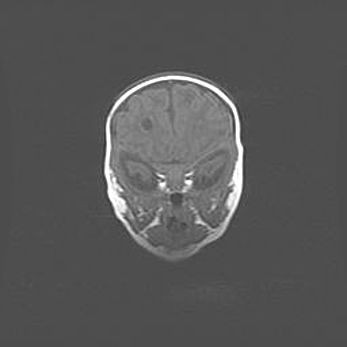

Наружная гидроцефалия с возможной атрофией височных областей.

Возраст: 28 дней

Вес: 3670 г

Пол: мужской

Окружность головы: 38 см

Срок гестации: 40 недель

Гидроцефалия головного мозга у новорожденных – это заболевание, которое характеризуется скоплением избыточного количества спинномозговой жидкости в желудочковой системе головного мозга в результате затруднения её перемещения от места выработки к месту поглощения в кровеносную систему или вследствие нарушения абсорбции. При открытой наружной форме гидроцефалии у новорожденных расширяются и переполняются субарахноидные пространства.

При нормотензивных  формах,  которые,  как  правило,  являются  следствием  перенесенных ишемических  повреждений  паренхимы  мозга,  возможно  сочетание микроцефалии  с нормотензивной гидроцефалией. В основе данных изменений лежит атрофия больших полушарий с преимущественной  локализацией  в  лобно-височных  областях.